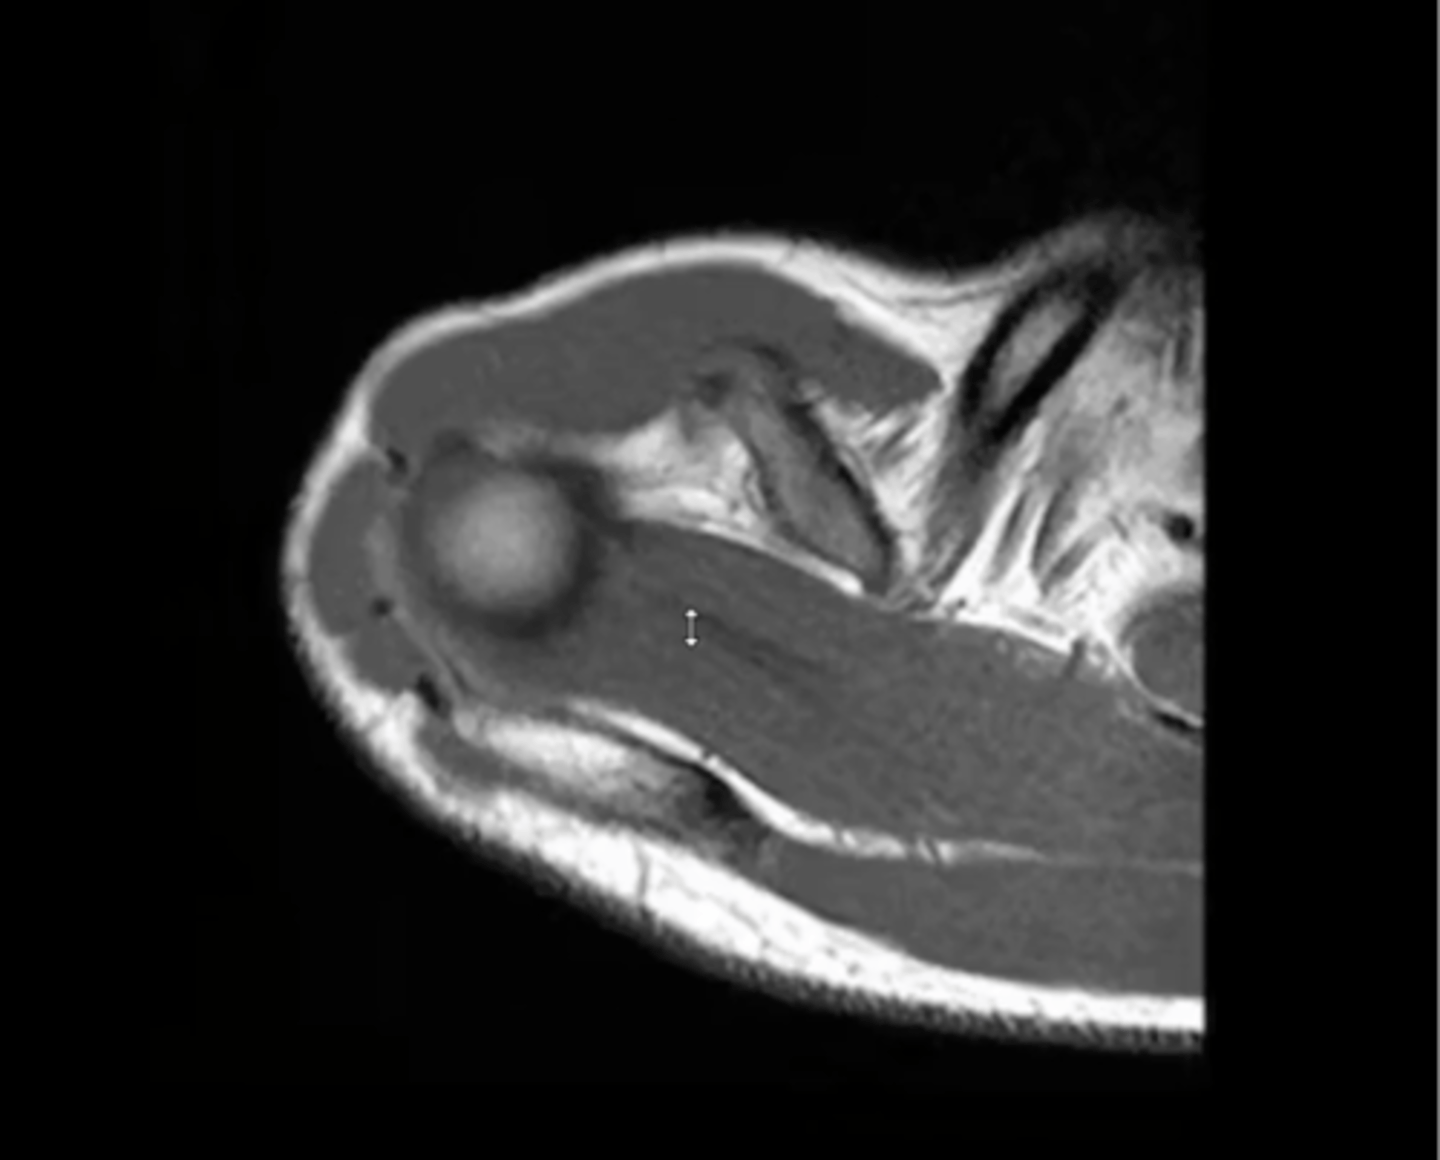

Axial view of the shoulder w/ atrophy of the subscapularis -- fat is depicted in white in the middle of the muscle, which is a tell-tale sign of disuse, atrophy, neurological impairments, or tendon tears

What is this image depicting? How do you know?